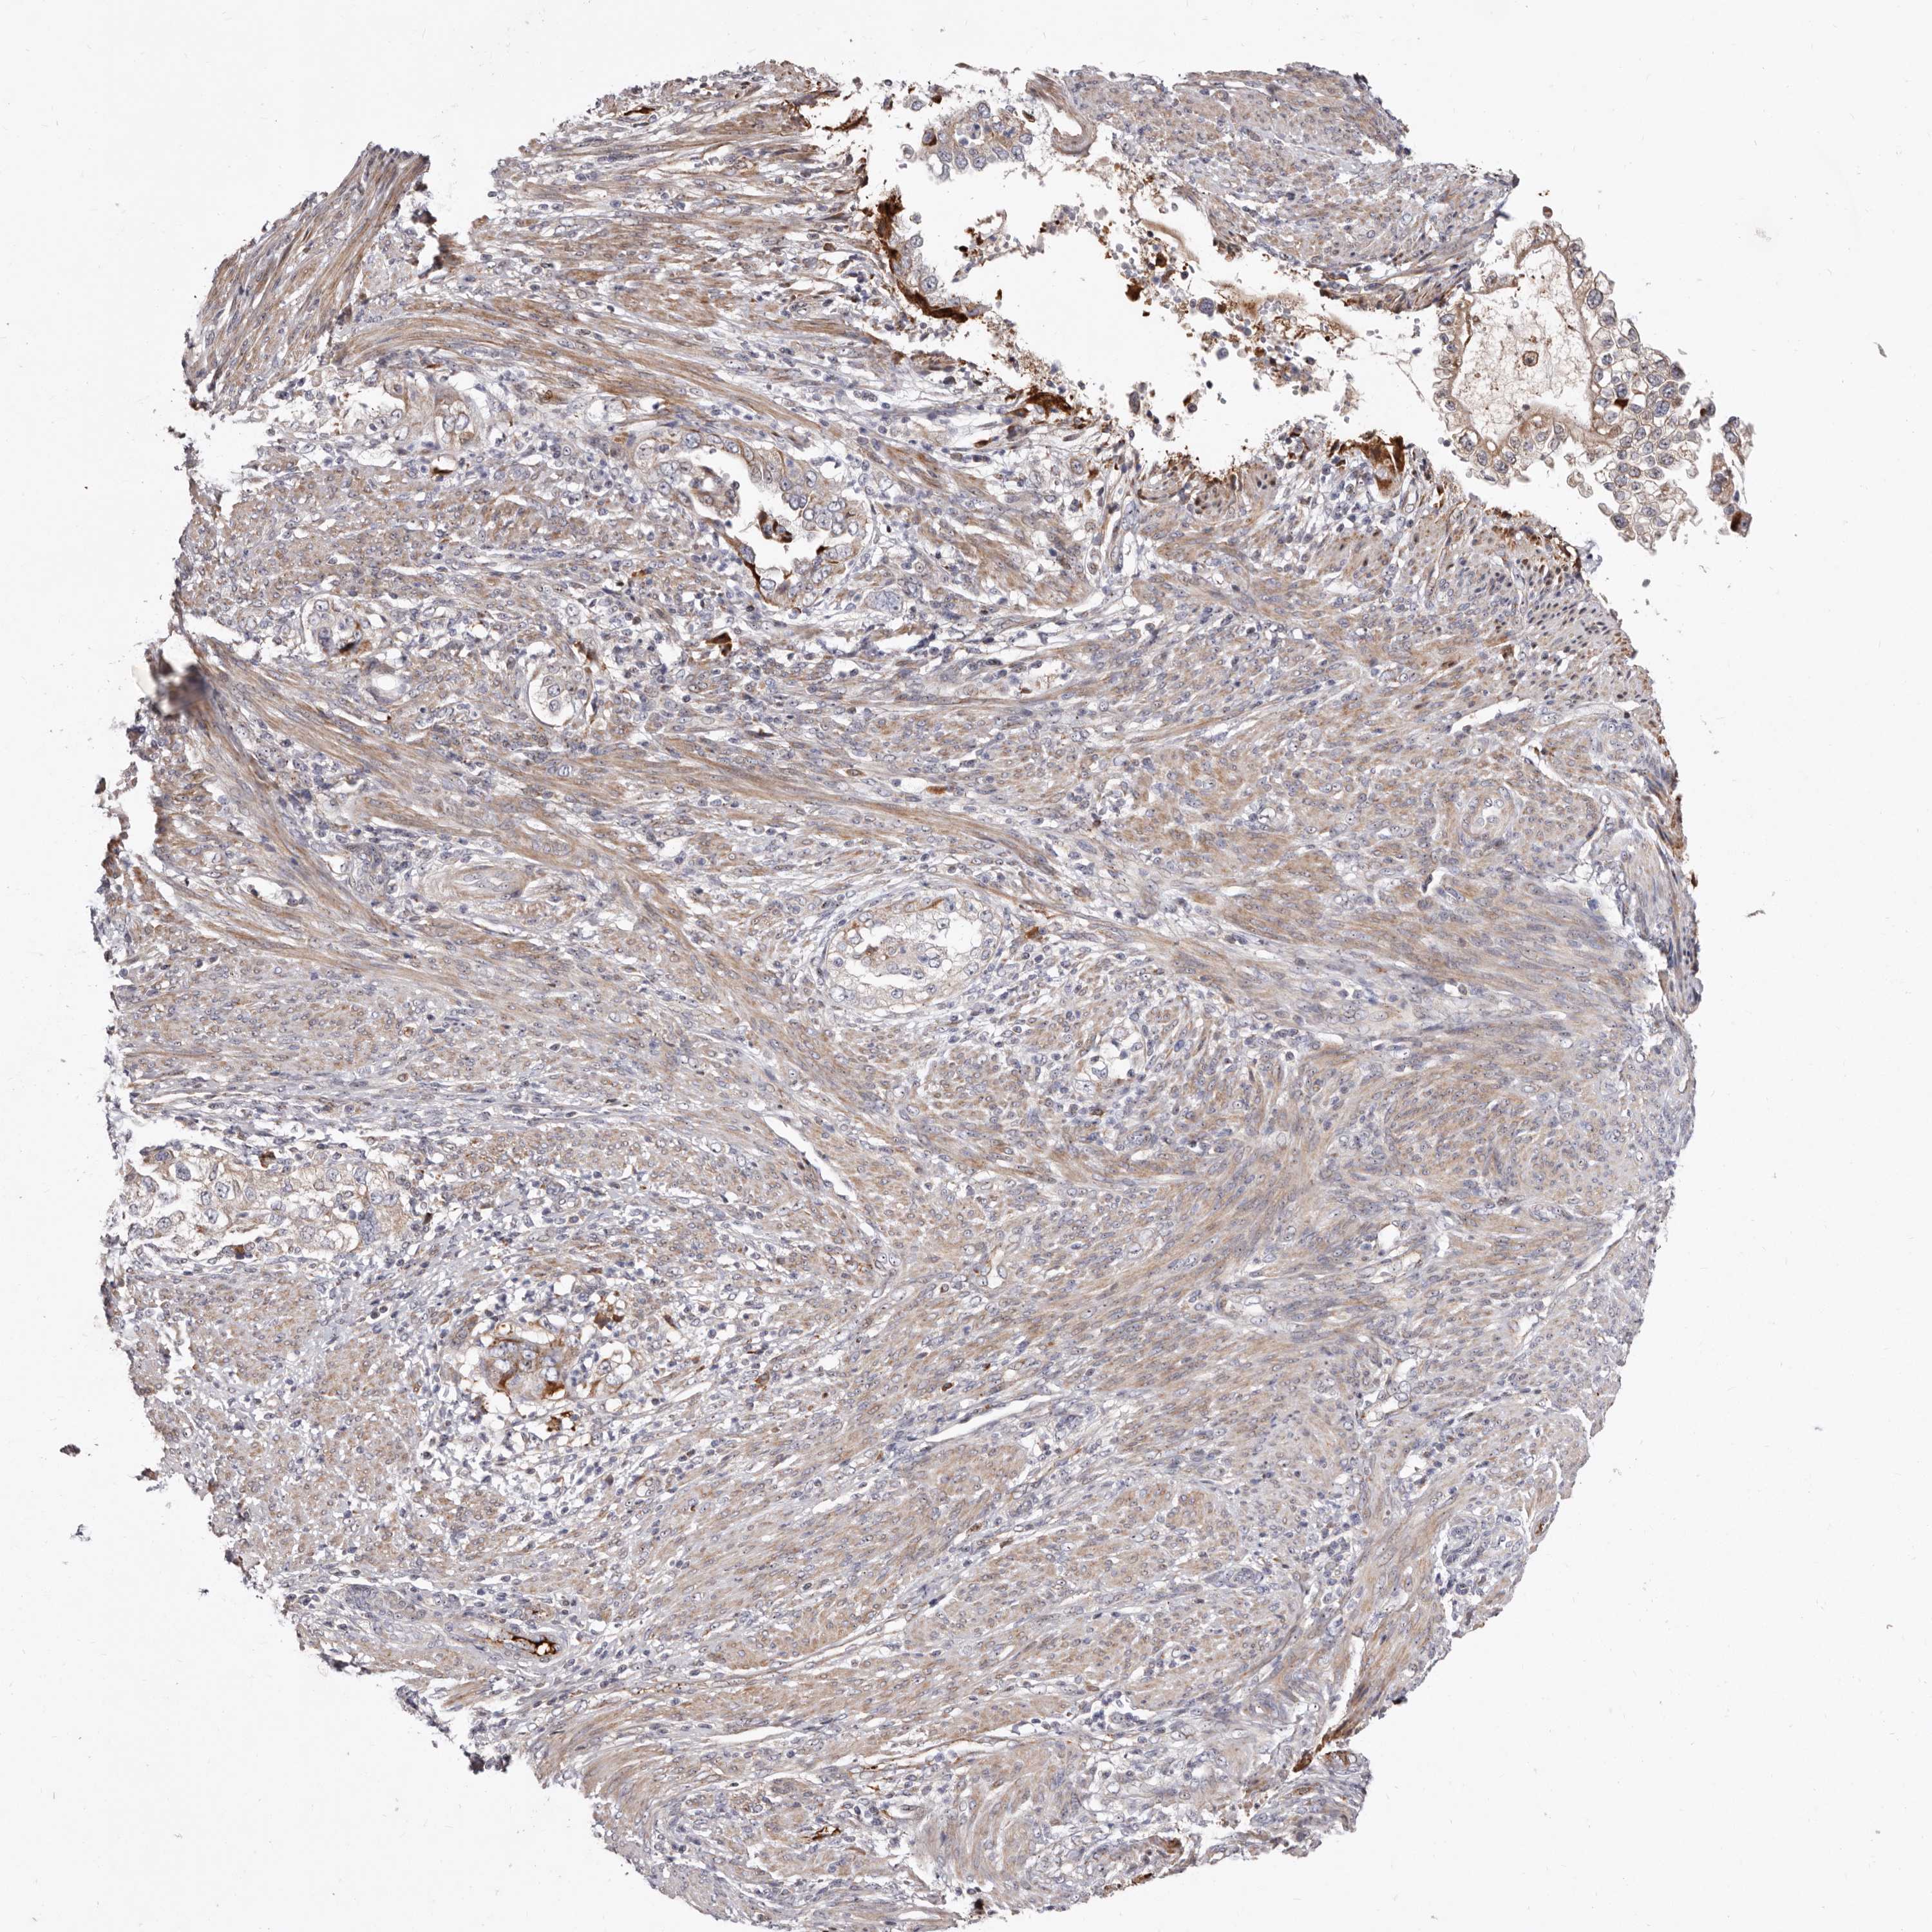

ENDOMETRIAL CANCER - Protein expressioni

A mouse-over function shows sample information and annotation data. Click on an image to view it in a full screen mode. Samples can be filtered based on level of antibody staining by selecting one or several of the following categories: high, medium, low and not detected. The assay and annotation is described here.

Note that samples used for immunohistochemistry by the Human Protein Atlas do not correspond to samples in the TCGA dataset.

Antibody stainingi

Antibody staining in the annotated cell types in the current human tissue is reported as not detected, low, medium, or high, based on conventional immunohistochemistry profiling in selected tissues. This score is based on the combination of the staining intensity and fraction of stained cells.

Each image is clickable and will lead to virtual microscopy that enables deeper exploration of all samples and also displays staining intensity scores, fraction scores and subcellular localization as well as patient and tissue information for each sample.

Antibody HPA029203

Staining

High

Medium

Low

Not detected

Intensity

Strong

Moderate

Weak

Negative

Quantity

>75%

75%-25%

<25%

None

Location

Nuclear

Cytoplasmic/membranous

Cytoplasmic/membranous,nuclear

Adenocarcinoma, NOS

Adenocarcinoma, metastatic, NOS